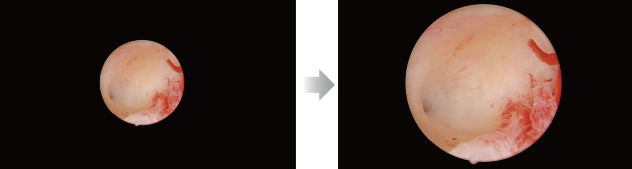

Reconocimiento automĂĄtico de imagen, ajuste de brillo inteligente

ExposiciĂłn inteligente: determine diferentes ĂĄreas de detecciĂłn en funciĂłn de diferentes escenarios y haga coincidir con precisiĂłn los parĂĄmetros de exposiciĂłn sin necesidad de cambiar manualmente los modos del escenario.

Imagen de endoscopio de peque?o diĂĄmetro (por ejemplo, histeroscopio)

Imagen del laparoscopio

Oscurecimiento automĂĄtico: el sistema de cĂĄmara puede ajustar automĂĄticamente la intensidad de la fuente de luz en tiempo real en funciĂłn de los requisitos de exposiciĂłn de la imagen actual y garantizar un brillo adecuado.

Zoom adaptativo automĂĄtico con un toque

El reconocimiento inteligente del tipo de endoscopio y el ajuste automĂĄtico con zoom adaptativo reducen la necesidad de realizar ajustes manuales repetidos y garantizan una visibilidad ideal para diferentes cirugĂas.

Endoscopio de peque?o diĂĄmetro: zoom adaptativo con un toque

Laparoscopio: pantalla completa con un toque